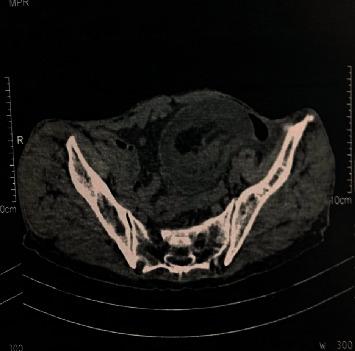

Acute intestinal invagination is the pathology of infants and small children. Its occurrence in adults is rare, and it represents 1 to 5% of intestinal occlusions often leading to the discovery of an organic cause that may be tumor. We report the case of a 72-year-old patient admitted to the emergency room of Ibn Sina Rabat, Morocco, for intestinal occlusion. The abdominal CT scan showed a voluminous intestinal invagination on a very probable heterogeneous digestive mass. The treatment was an open right hemicolectomy. The histopathological examination of the surgical specimen concluded a colonic well-differentiated adenocarcinoma with a 30% mucinous component. By review of literature, we discuss diagnostic and therapeutic procedures in emergency.